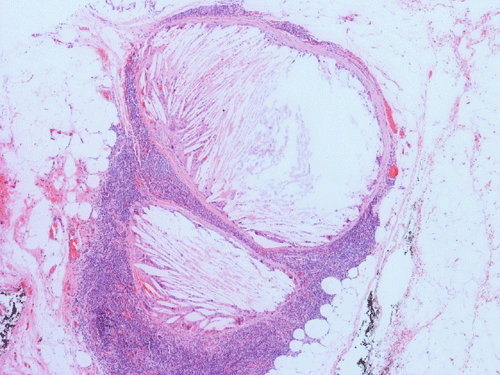

Clinical information: The patient is a 36 year-old woman who presented with a 2 cm swelling in the left side of her neck. The mass was not tender, warm, or painful. The overlying skin was unremarkable. A CT scan was performed and showed a 1.8 x 1.2 cm relatively non-enhancing lesion within the carotid sheath displacing the carotid artery anterioriorly. The clinical and imaging features yielded an empirical diagnosis of an enlarged lymph node. The patient had no history of lymphoma, leukemia, or head and neck tumor. The mass was removed surgically in its entirety and was 2.5 cm in maximum dimension, well encapsulated, located at the level of the carotid bifurcation just lateral to the carotid artery and superiorly extending almost up to the level of the tonsils. The mass did not appear to be in continuity with the jugular vein or the carotid artery. It was not a part of the vagus nerve or sympathetic chain. The followings are representative images.